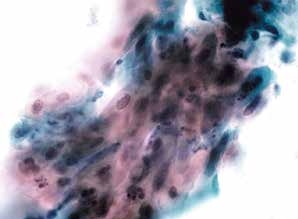

图4-31 高度鳞状上皮内病变(HSIL)(高倍、液基、巴氏染色)

异型增生的细胞密集成团,胞核明显增大,核膜不规则,核质比明显增高。

图4-32 高度鳞状上皮内病变(HSIL)(高倍、液基、巴氏染色)

细胞核异型性明显,染色质粗颗粒状,核膜不规则,胞质浓染,核质比高。此为异型性明显的不成熟化生细胞,判读为HSIL。